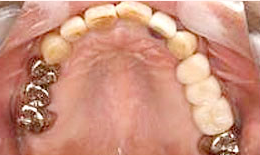

治療後

上顎

インプラントを2本埋め込んで、セラミックスクラウンを被せた

上部構造

(ハイブリッドクラウン)8本

135,000×8=1,080,000円(税抜)